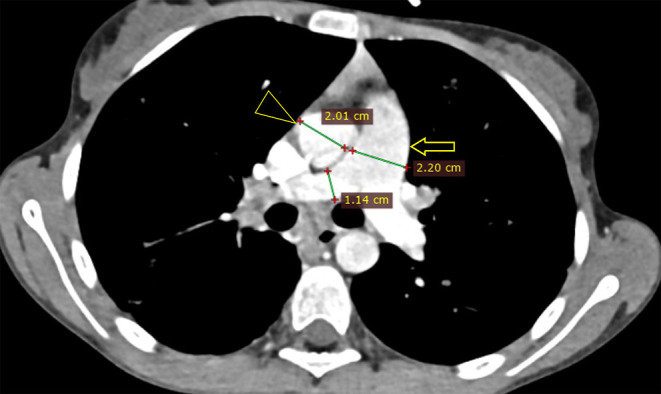

囊性纤维化(CF)是一种多系统疾病,是由于第 7 号染色体上的 CF 跨膜传导调节器(CFTR)基因突变导致的常染色体隐性先天性遗传。由于该病被认为是高加索儿科人群的疾病,或者由于缺乏认识,像我国这样的发展中国家很少考虑该病。本病例报告是埃塞俄比亚(也可能是东非)报告的首例囊性纤维化病例,患者是一名 17 岁女性,在对其腹部和胸部进行 CT 扫描后确诊患有该病。由于她长期咳嗽,最初被误诊为肺结核(TB)并接受治疗。也许是由于流行病学证据,在埃塞俄比亚,几乎所有慢性咳嗽伴有肺实质纤维支气管扩张病变的病例都被顽固地归咎于肺结核(TB)。一旦对这些病人做出结核病诊断,他们的诊断就会陷入结核病再感染、复发或耐药的怪圈,随后又要接受多个阶段的抗霉菌药物治疗。这可能会导致危险的影响,包括不必要的长期抗霉菌治疗、产生耐药性的可能性以及与管理不当有关的患者发病率。该患者的胸部和腹部 CT 结果,包括支气管扩张、肝脂肪变性、胰腺脂肪瘤、微小胆囊和近端结肠壁增厚,导致了 CF 的诊断。这篇文章介绍了该地区第一例有记录的 CF 病例,旨在提醒临床医生和放射科医生也要考虑像 CF 这样可能 "罕见 "的疾病,而不是把每一次慢性咳嗽都归咎于肺结核,并强调了腹部 CT 特征在 CF 诊断中的重要性。

Cystic fibrosis (CF) is a multisystem disorder that occurs as a result of autosomal recessive congenital transmission of CF transmembrane conductance regulator (CFTR) gene mutation on chromosome 7. Because it is considered a disease of the Caucasian pediatric population or due to lack of awareness, it is rarely considered in developing countries like ours. This case report presents the first case of cystic fibrosis ever reported in Ethiopia and possibly East Africa, that of a 17-year-old female diagnosed with the disease following a CT scan of her abdomen and chest. She was initially misdiagnosed and treated for tuberculosis (TB) as she was a chronic cougher. Perhaps due to epidemiological evidence, there is an obstinate tendency of blaming tuberculosis (TB) for almost every case of chronic cough with fibro-bronchiectatic lung parenchymal changes in Ethiopia. Once a diagnosis of TB is posted on such patients, their diagnosis remains in the circle of TB reinfection, relapse or resistance, followed by multiple phases of anti-mycobacterial drugs. This could lead to hazardous implications, including unnecessary prolonged anti-mycobacterial treatments, possibility of developing drug resistance, and mismanagement-related patient morbidity. This patient's chest and abdominal CT findings, including bronchiectasis, hepatic steatosis, pancreatic lipomatosis, micro-gallbladder and proximal colonic wall thickening, led to the diagnosis of CF. This article, presenting the first documented case of CF in the region, is meant to be a helpful reminder for clinicians and radiologists to also consider presumably "rare" illnesses like CF rather than blaming TB for every chronic cough and highlights the importance of abdominal CT features in the diagnosis of CF.